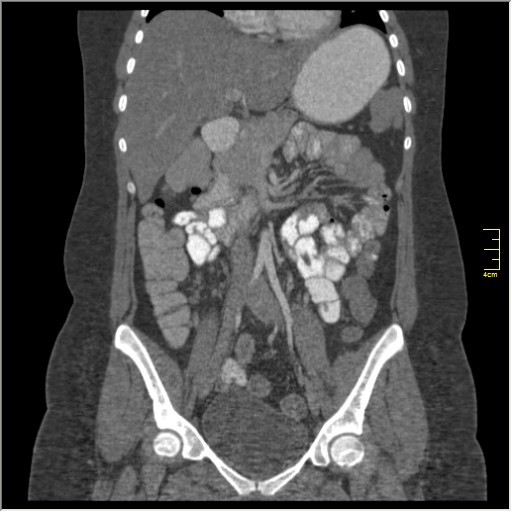

Демонстрационные изображение, оцените возможности метода! Толщина среза реконструкции 0.5-1 мм.